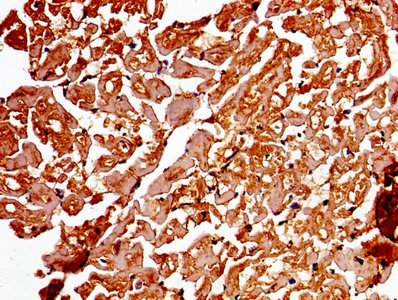

Immunohistochemistry of paraffin-embedded human heart tissue using CSB-PA001311LA01HU at dilution of 1:100

IHC image of CSB-PA001311LA01HU diluted at 1:250 and staining in paraffin-embedded human lung tissue performed on a Leica BondTM system. After dewaxing and hydration, antigen retrieval was mediated by high pressure in a citrate buffer (pH 6.0). Section was blocked with 10% normal goat serum 30min at RT. Then primary antibody (1% BSA) was incubated at 4°C overnight. The primary is detected by a biotinylated secondary antibody and visualized using an HRP conjugated SP system.